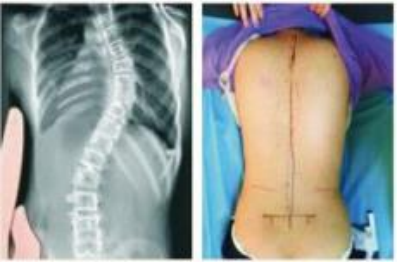

住院过程中最温暖人心的是彼此的信任和理解,所以飞飞经过不到1个月的治疗身体已经有了明显的改善,两侧腰背部平整度明显恢复,肌肉僵硬状态已好转,复查X线显示:脊柱基本居中,病情好转,予以出院。

治疗前后对比图:

飞飞的治疗已经取得了理想的效果,小伙子满脸洋溢着笑容。相信只要飞飞能够坚持锻炼并严格遵循医嘱,他日后一定可以拥有一个健康的体态和挺拔的脊柱,想去当兵也没有任何问题!